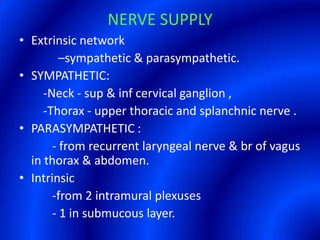

This document provides information about a barium swallow procedure. It begins with an introduction and overview of the embryology and anatomy of the pharynx and esophagus. It then describes the procedure itself, including preparation, technique, views obtained, and indications. Specific conditions that may be examined include pharyngeal and esophageal webs, foreign body impaction, scleroderma, dysphagia, mediastinal masses, and carcinoma. Diagrams are provided to illustrate normal anatomy and various pathological findings.